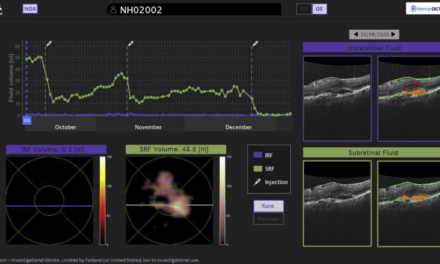

Se está utilizando la inteligencia artificial en el campo de la oftalmología para la detección temprana de enfermedades oculares. Los algoritmos permiten segmentar imágenes correspondientes a ojos sanos y ojos con patologías, lo que posibilita que el sistema identifique de manera instantánea la presencia de problemas oculares al ingresar una fotografía del ojo de un paciente. Además, estos sistemas también se emplean en la detección temprana de retinopatía diabética y degeneración macular asociada a la edad (DMAE). La detección precoz de estas enfermedades resulta crucial para ralentizar su progresión.

En la oftalmología, la inteligencia artificial se emplea a través de algoritmos que analizan imágenes del fondo de ojo, capturadas con una cámara retinal y enviadas a la nube. Estos algoritmos son capaces de detectar y monitorear diagnósticos en cuestión de minutos, lo que mejora la eficiencia del tratamiento y evita intervenciones innecesarias en el futuro.